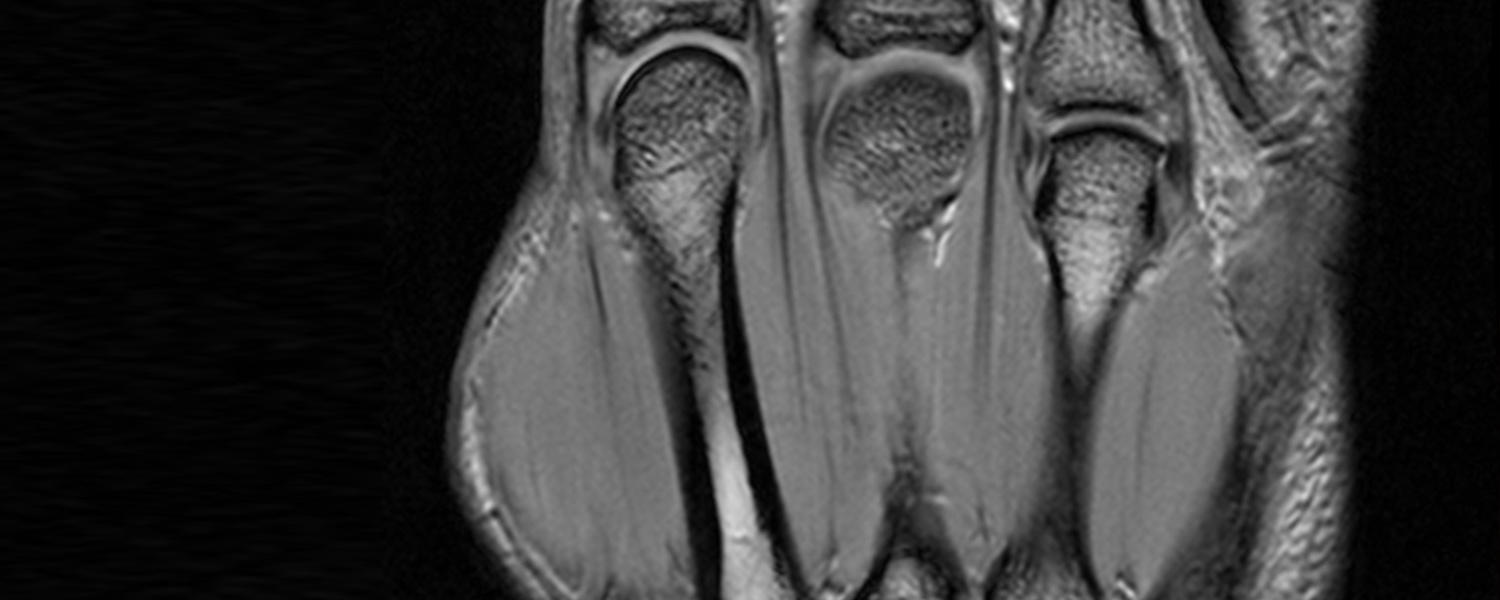

The Musculoskeletal Radiology fellowship at the University of Calgary is a one year fellowship which provides comprehensive training in imaging of diseases of the musculoskeletal system, including sports injuries, trauma, orthopedic oncology, and arthritis.

Training encompasses all aspects of MSK imaging: Radiography, CT, MRI, ultrasound, and interventional procedures. The procedural component of the fellowship primarily includes arthrography, joint aspiration and biopsy but there are also the opportunities to become involved in procedures such as nerve blocks, osteoid osteoma ablation and kyphoplasty. Fellows are also encouraged to become involved in our busy MSK ultrasound practice which performs a significant volume of diagnostic MSK US studies each day, as well as US-guided procedures including tenotomies, PRP injections, lavage of calcific tendinosis, nerve blocks, flexor retinaculum release for carpal tunnel, trigger finger injections etc.